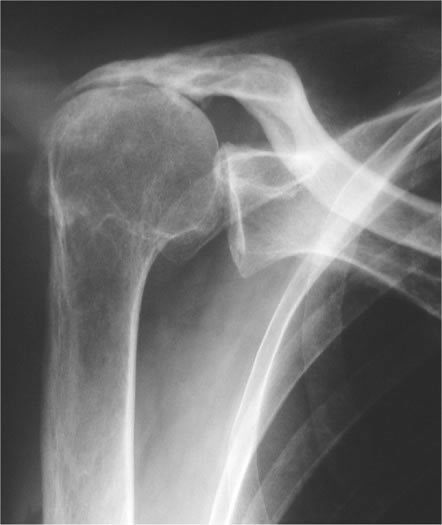

• Röntgenbilder (Nachweis einer Gelenkspaltverschmälerung, Nachweis von knöchernen Anbauten, exakte Beurteilung des Pfannenverschleißes)

Unter Schultergelenksarthrose (Omarthrose) verstehen wir den Verschleiß des Schultergelenkes durch eine Verminderung und Zerstörung der Knorpelsubstanz. Im Extremfall reiben Oberarmkopf und Gelenkpfanne knöchern aufeinander, was zu einer stark schmerzenden Schulter mit Gelenkentzündung und Bewegungseinschränkung führt.

Typische Beschwerden sind Bewegungseinschränkung, besonders für Rotationsbewegungen, Ruheschmerz, Bewegungs- und Belastungsschmerz, sowie Reiben und Knirschen bei sämtlichen Schulterbewegungen. Oft liegen auch Schwellungszustände mit Ergussbildung vor.